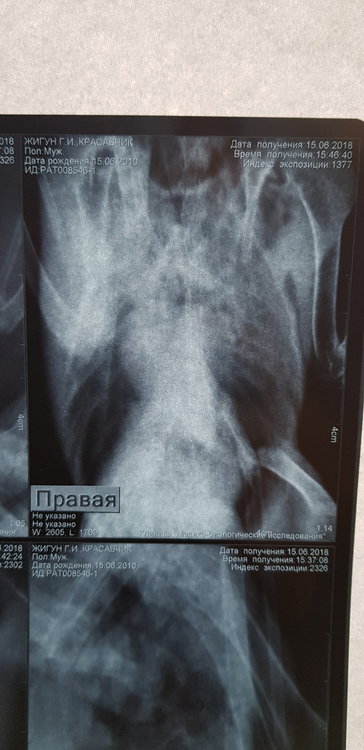

Сделала рентген. Но я в нем не разбираюсь.  Есть ли там грибы в легких. 3 дня по чуть-чуть совсем так чтобы выходило примерно 5 по на день орунгамин. И сейчас ему совсем плохо. Один глаз закрыт, помутнеет. Постоянно пытается отрыгнуть или делает такие движения. Совсем вялый. Фото прикреплю в сообщении ниже